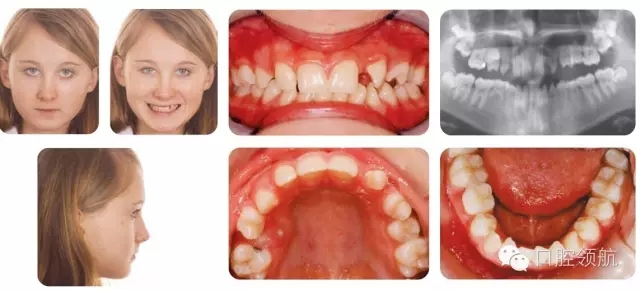

12歲的女性患者,為II類2分類錯牙合,中度骨性II類,后縮側(cè)貌,下頜發(fā)育不足(圖2.23)。

圖2.23

臨床牙列情況

哪顆牙缺失?

X線片檢查顯示UL3和LR5先天缺失,LRE滯留,預后較好。

該病例的主要問題是什么?

● Ⅱ類切牙關(guān)系。

● UR5和下切牙擁擠。

● 上頜第一前磨牙扭轉(zhuǎn)。

● 上頜后牙段間隙。

● UL3和LR5先天缺失。

● LRE滯留(預后較好)。